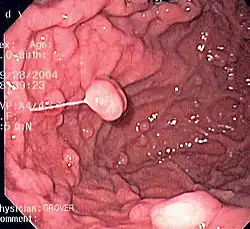

A series of radiographs can be used to examine the stomach for various disorders. This will often include the use of a barium swallow. Another method of examination of the stomach, is the use of an endoscope. A gastric emptying study is considered the gold standard to assess the gastric emptying rate.[50]